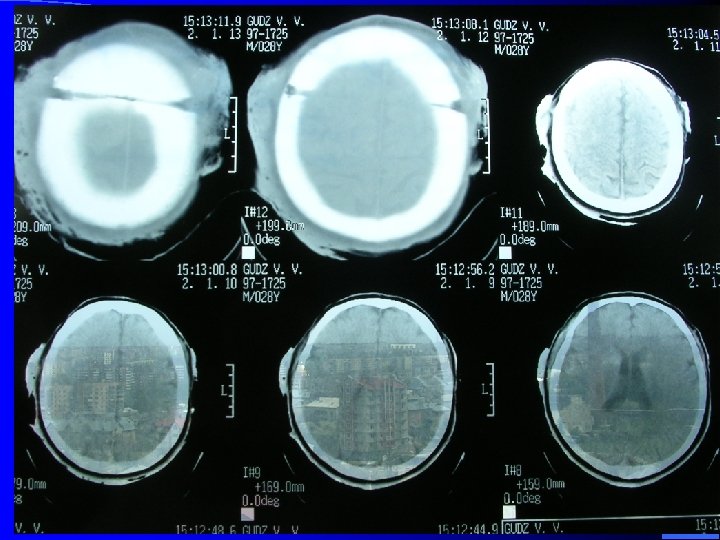

l Дифузное аксональное повреждение: l Синдром функционального или анатомического розобщения большых полушарий и ствола мозга. l Клинка: l Продолжительная кома с момента ЧМТ; l Переход комы у вегетативное состояние; l Горметония, гипотония; l Пирамидные и екстрапирамидные парезы конечностей; l Лицевые синкинезии (моргание глаз, жевание, скрежет зубов); l Четкая вегетативная симптоматика.

Диагностика: l АКТ (МРТ): увеличение обема мозга, сдавлени боковых и ІІІ желудочка, цыстерн, субарахноидальных пространств, мелкоочаговые геморагии в белом веществе, подкорке, стволе. l